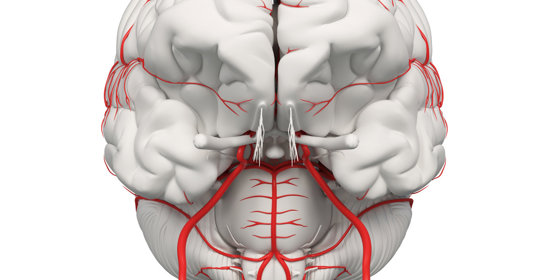

大腦與神經

腦幹梗塞:前兆、原因、後遺症及治療方法

腦幹梗塞:診斷與治療

腦幹梗塞:原因、症狀及治療方法

腦幹梗塞:症狀、恢復及預防